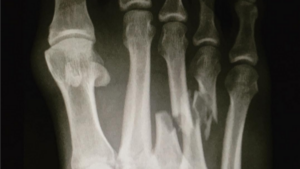

Kelly Slater se blesse au pied à J-Bay

Les prochaines échéances sont sérieusement compromises pour le Floridien.